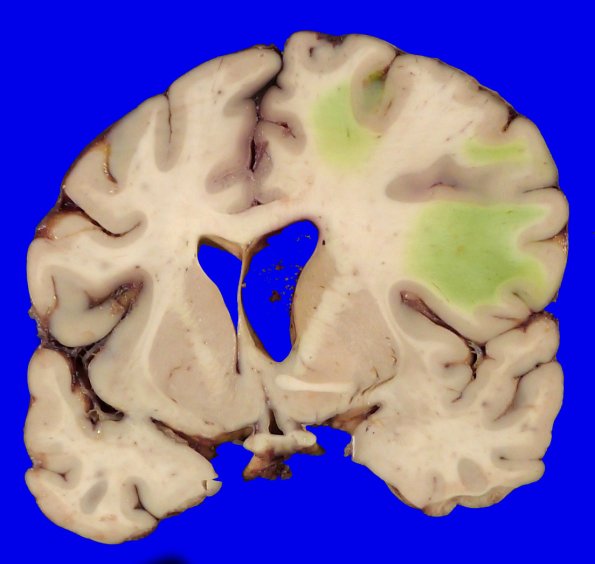

Washington University Experience | VASCULAR | Hemorrhage, hypertensive | 49B2 A20-76_7

At this level the right hemisphere shows edema, right ventricular dilatation and bilirubin staining of the white matter as a response to hemorrhage-induced vascular leakage in adjacent regions.